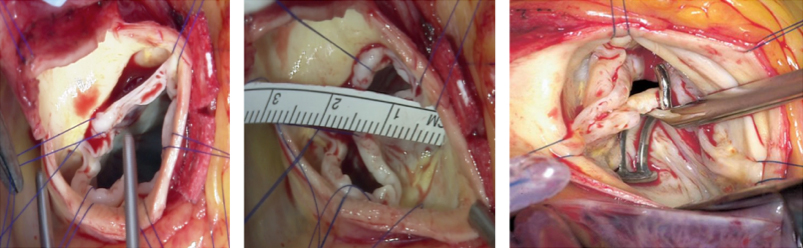

拡張型心筋症に対する僧帽弁複合体再建(PMTA法)の部分図

当科では機能性僧帽弁閉鎖不全症(虚血性心筋症や拡張型心筋症などにともなう僧帽弁閉鎖不全症)に対する外科治療に積極的に取り組んで参りました。近年、当科の松居らにより弁置換術に僧帽弁複合体再建法を組み合わせたPMTA(Papillary Muscle Tugging Approximation)法を報告いたしました(Matsui et al. Annals of Thoracic Surgery 2019; 107: e 427-9)。今後とも機能性僧帽弁閉鎖不全症の治療、特に年齢などの理由から心移植適応が難しい患者の方の治療にも積極的に取り組んで参ります。